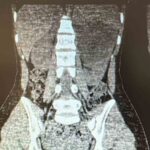

Şanlıurfa Viranşehir Devlet Hastanesi’nde, 18 yaşındaki bir hastanın sol böbreğinde tespit edilen yaklaşık 10 santimetre çapındaki kist, laparoskopik (kapalı) yöntemle başarıyla çıkarıldı.

Uzun süredir sol yan ağrısı şikâyeti çeken kadın hasta, dış merkezde yapılan tetkiklerde sol böbrekten kaynaklanan, böbrek ve dalağı iterek komşu organlara yapışıklık gösteren büyük bir kistin varlığının tespit edilmesi üzerine Viranşehir Devlet Hastanesi’ne sevk edildi. Hastanede yapılan değerlendirmeler sonucunda kistin cerrahisi için karar alındı.

Üroloji kliniğinde gerçekleştirilen operasyonda, 10 santimetre boyutundaki böbrek kisti laparoskopik yöntemle, 2 adet 5 milimetre ve 1 adet 10 milimetrelik kesi kullanılarak çıkarıldı. Böylece hasta, açık cerrahiye ihtiyaç duymadan tedavi edildi. Ameliyat sonrası takiplerinde herhangi bir komplikasyon gelişmeyen hasta, sağlığına kavuşarak taburcu edildi.